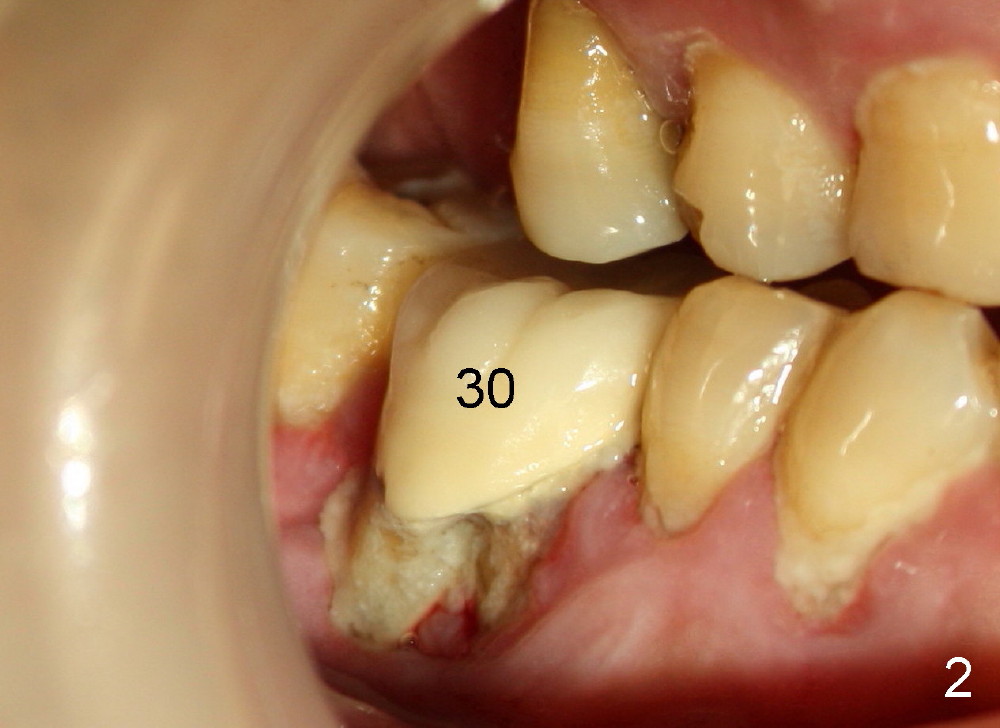

A 46-year-old man has severe periodontitis. The tooth #30 is complicated by incomplete root canal therapy (Fig.1,2). Three months after extraction (Fig.3-5: N: inferior alveolar canal), a 5x14 Tatum tapered implant is placed (Fig.6,7). The problem is that an implant driver is fractured (D in Fig.7), while the implant is being torqued. It takes time and effort to remove the fractured driver, but the implant is solid. The healing screw is placed without difficulty (Fig.8). Since the implant is placed lower than the lingual gingiva (L in Fig.9), a healing cuff is placed 1.5 months after implant placement (Fig. 10 and 11: C) to push the lingual gingiva down. The X-ray appears to show lower bone density around the implant (bone necrosis?), although the implant has no mobility at all. Since the implant is so solid, can we load it, two months after surgery? The lingual gingiva is now lower than the healing cuff (not shown). CT is scheduled to be taken tomorrow. Thanks.